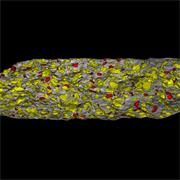

- Fast, quantitative analyses of entire tablets and powder blends

- Determine the uniformity of mixing

Ensure your chemical images are representative; use Renishaw's StreamLine. You can change resolution to suit your domain size and, because Renishaw's WiRE software can cope with massive data files, you can analyse over the entire sample surface. Powerful Renishaw features, such as Slalom (to ensure the whole surface is sampled) and HD imaging (to get crisp clear images), provide all the options you need, whatever your formulation.